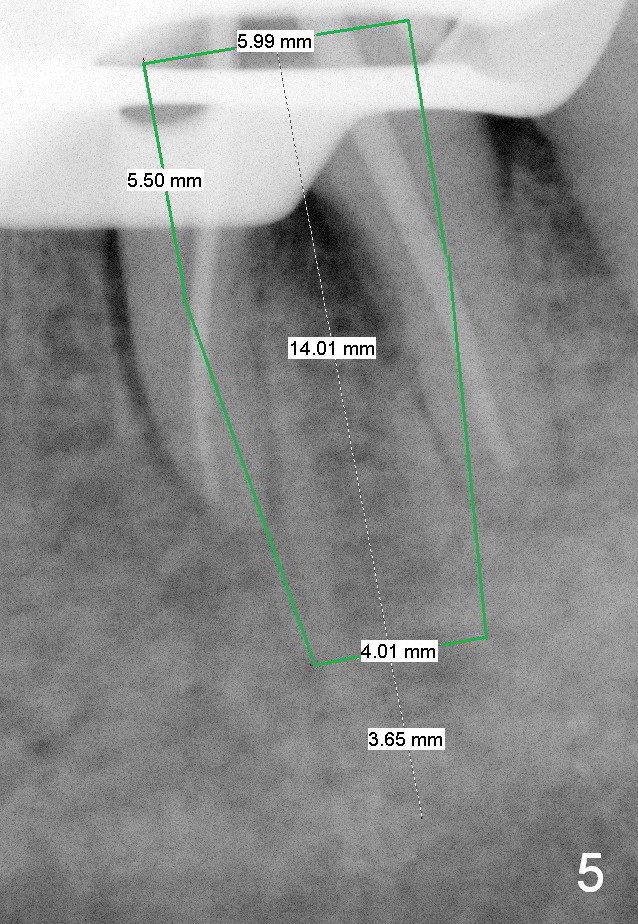

A 59-year-old lady has history of periodontal disease and bruxism. The tooth #19 has pulpitis after unsuccessful DO composite (Fig.1 *) and requires root canal therapy (Fig.2). Six months later, a fistula is found to communicate with the furca (Fig.3 *: gutta percha). Less than 3 years, the furca enlarges with symptoms of infection (Fig.4 *). She works out of state. The Principle of No Implant, No Extraction is adhered. Since she is of short statue, the bone height is relatively limited. A 6x14 mm tissue-level implant is appropriate (Fig.5, one piece). Sensor 1 may be proper for her small mouth. When the bottom of the socket is large and close to the Inferior Alveolar Nerve, can an immediate implant be placed?